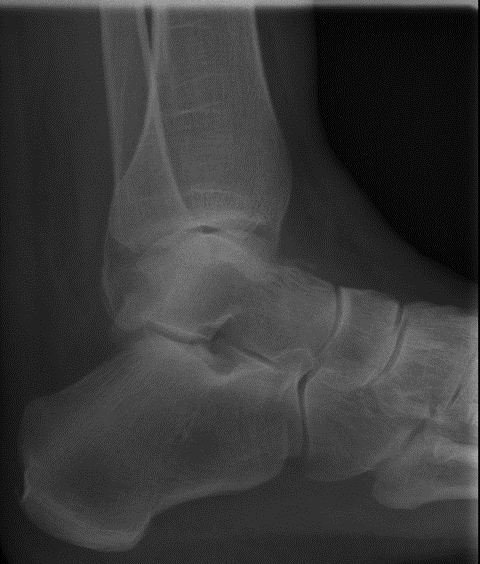

Die Röntgenuntersuchung ergab keinen pathologischen Befund. (Abb.1 und 2)

Abb.2 Unfallbild seitlich